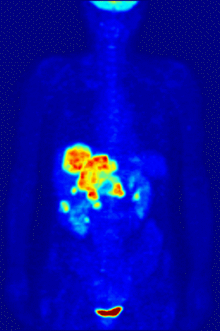

If the biologically active molecule chosen for PET is fludeoxyglucose (FDG), an analogue of glucose, the concentrations of tracer imaged will indicate tissue metabolic activity as it corresponds to the regional glucose uptake. Use of this tracer to explore the possibility of cancer metastasis (i.e., spreading to other sites) is the most common type of PET scan in standard medical care (90% of current scans). However, although on a minority basis, many other radioactive tracers are used in PET to image the tissue concentration of other types of molecules of interest. One of the disadvantages of PET scanners is their operating cost.[2]

Oncology

PET scanning with the tracer fluorine-18 (F-18) fluorodeoxyglucose (FDG), called FDG-PET, is widely used in clinical oncology. This tracer is a glucose analog that is taken up by glucose-using cells and phosphorylated by hexokinase (whose mitochondrial form is greatly elevated in rapidly growing malignant tumors). A typical dose of FDG used in an oncological scan has an effective radiation dose of 14 mSv.[3] Because the oxygen atom that is replaced by F-18 to generate FDG is required for the next step in glucose metabolism in all cells, no further reactions occur in FDG. Furthermore, most tissues (with the notable exception of liver and kidneys) cannot remove the phosphate added by hexokinase. This means that FDG is trapped in any cell that takes it up, until it decays, since phosphorylated sugars, due to their ionic charge, cannot exit from the cell. This results in intense radiolabeling of tissues with high glucose uptake, such as the brain, the liver, and most cancers. As a result, FDG-PET can be used for diagnosis, staging, and monitoring treatment of cancers, particularly in Hodgkin's lymphoma, non-Hodgkin lymphoma, and lung cancer.